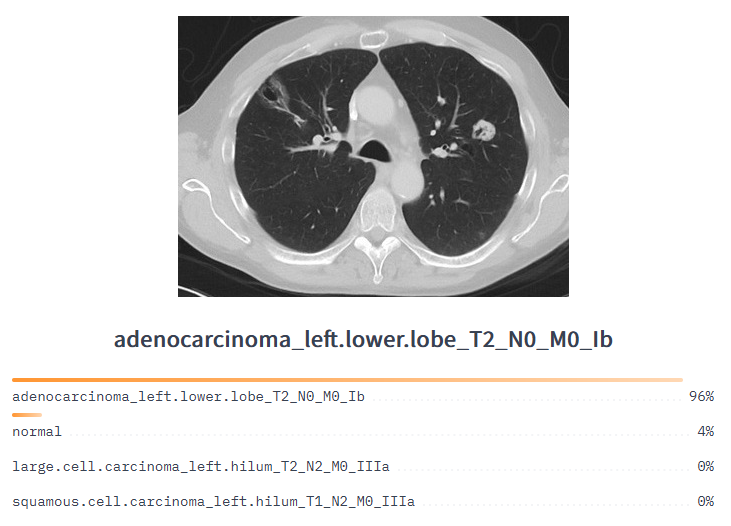

With the rapid improvements in technology, healthcare computer vision systems may be used for diagnosing other types of cancer, including bone and lung cancer, in the near future.

Lung cancer classification model to analyze CT medical imaging